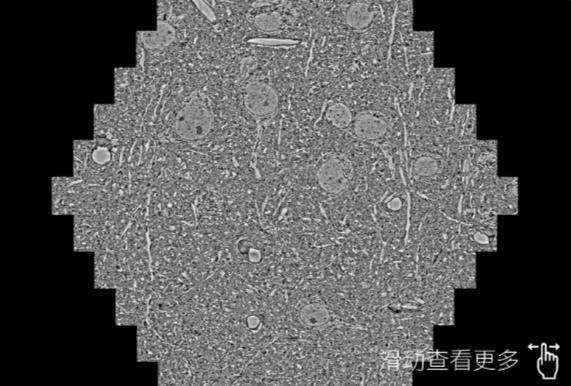

鼠脑切片。左图使用玉林蔡司玉林扫描电镜MultiSEM706对165μmx143pm面积区域成像,耗时仅需1.5秒。右图为鼠脑切片中30μm区域放大效果。样品由芝加哥大学B.Kasthuri提供。

使用蔡司高速玉林扫描电镜MultiSEM对1mm²人脑皮层组织进行高分辨成像,并对其中的各种细胞结构进行三维重构分析。左图展示了2x3mm²组织平面中锥体神经元的三维重构效果。右图显示了局部体积神经元三维重构。图像由哈佛大学chtman实验室提供,渲染图由D. Berger 制作。